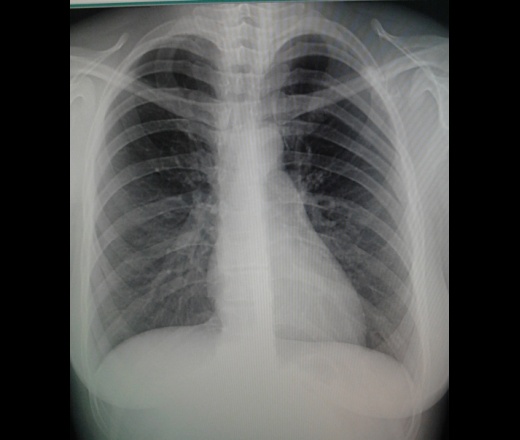

Девушка,1989 г.р.жалоб нет никаких,со слов в том году проходила флг(не у нас)-норма.Вызвала на рск,покрутила-тень смещается вместе с лопаткой,с ребрами не связана.Что это может быть слева на лопатке?остеохондрома?

Поддерживаю остеохондрому

+1.Но, для уточнения попытался  бы просмортреть ФЛО-архив, в плане динамики изменений  (  можно предположоить, что изменения имели место , но были пропущены, хуже если их правда не было...) Может помочь сбор жалоб и анамеза заболевания.  Показана КТ  органов грудной клетки.

Я бы изменения именовал остеомой. И без архива, без жалоб назначил бы... плановый рентген-контроль...